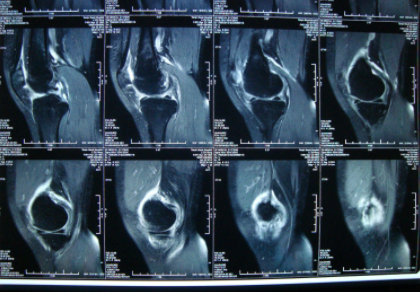

又过了几天情况越发严重,实在没办法我才去了市里的骨科医院,医生先让我去拍ct,当天下午就取到了片子,医生看了后表示无明显异常,又让我去做了个核磁共振检查,第三天下午才拿到结果,当时医生就表示我的膝盖里面有积液,诊断结果就是滑膜炎。